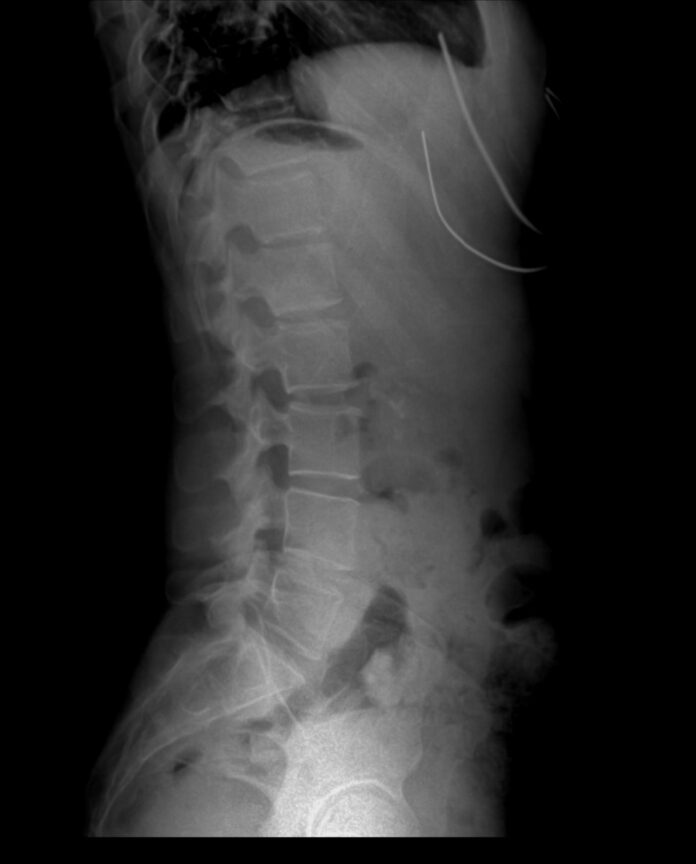

흉곽출구증후군(TOS)은 목과 어깨 사이 흉곽출구라는 공간을 지나는 신경이나 혈관이 압박을 받으면서 생기는 증상이다.